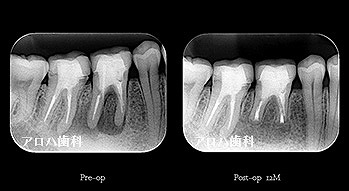

case10

左上に腫脹、圧痛

根尖部に透過像

術前、術直後、予後

術前、術後